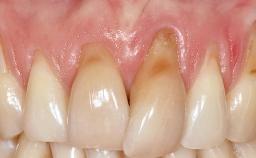

A 30-year-old woman was referred by her general dentist for evaluation of an esthetic complication related to previous implant treatment for congenitally missing maxillary lateral incisors. The patient’s chief complaint was the inadequate esthetic appearance of her smile. The case demonstrates the use of a combined approach to achieve optimal results. Two different flap designs - a tunnel technique and a coronally advanced flap - are employed based on the surgical objectives for the affected site.

Soft Tissue Grafting Yes

Soft Tissue Anatomy Intact Defective